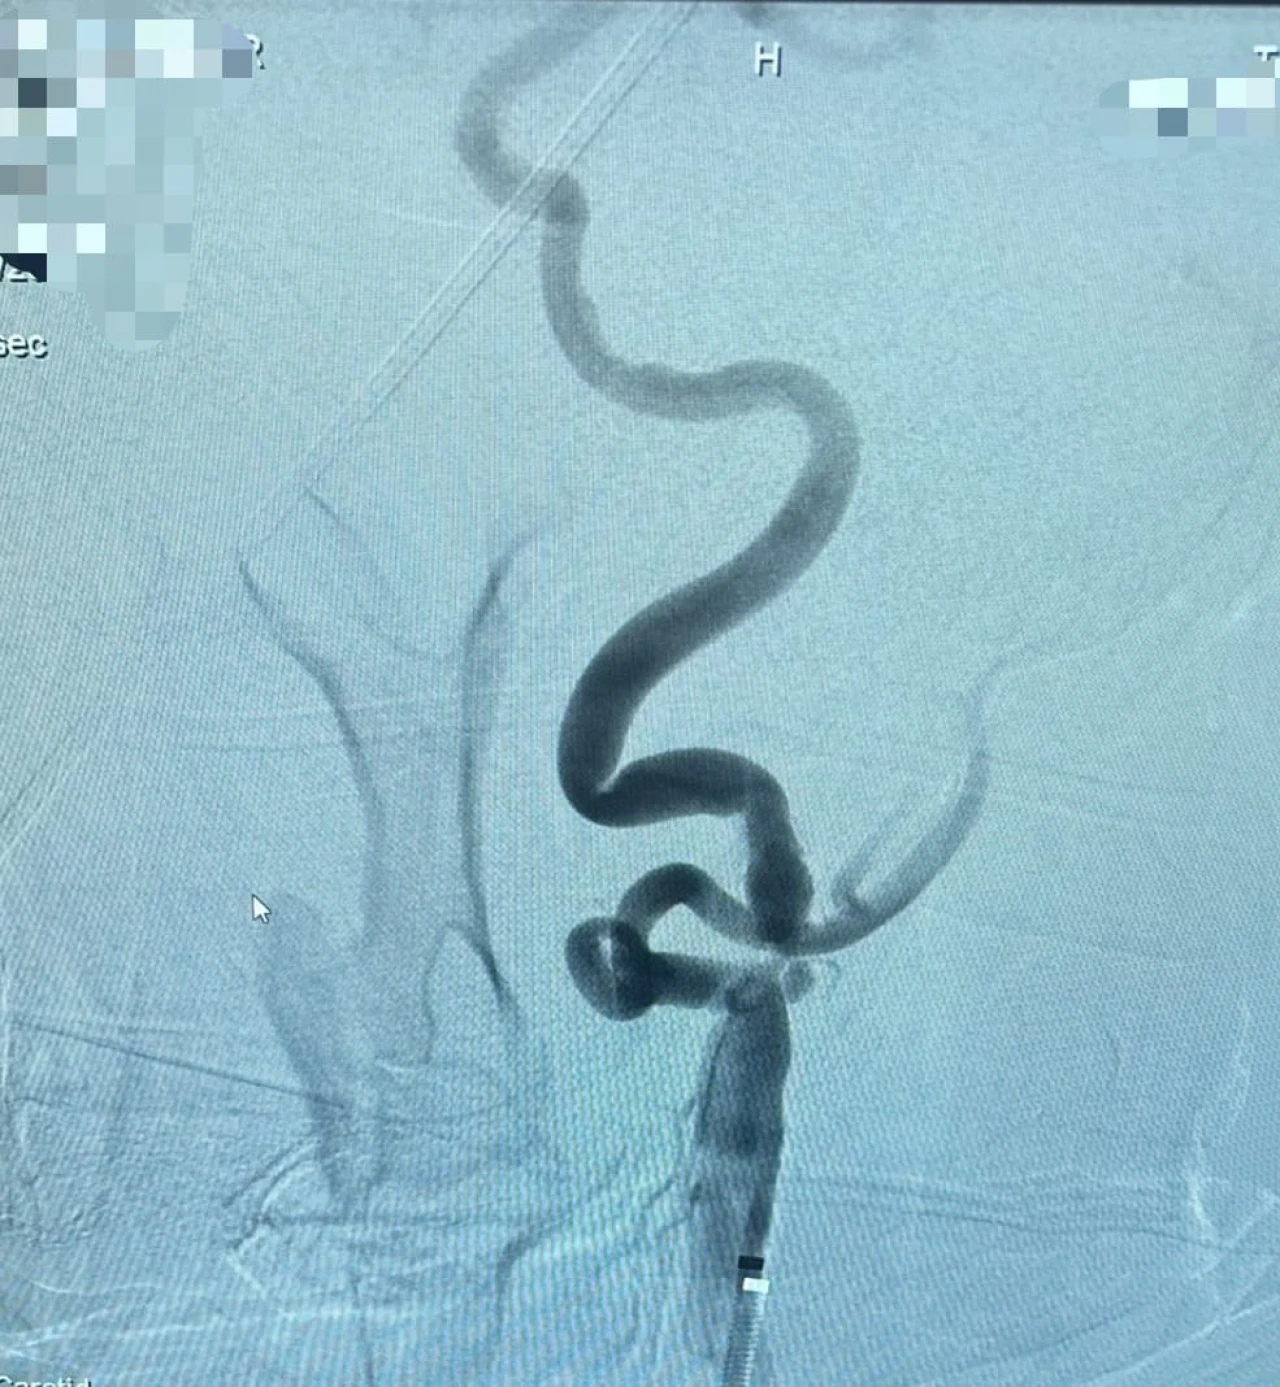

Şah damarında tespit edilen darlık, özel bir balonla genişletilir ve ardından stent adı verilen ince bir metal kafes yerleştirilerek damarın açık kalması sağlanır. Bu sayede kan akışı normale döner ve felç geçirme riski önemli ölçüde azalır. İşlem, ameliyat gerektirmeden anjiyografi ünitesinde yapılır.

Girişimsel Radyoloji Uzmanı Dr. Öğretim Üyesi İsmail Taşkent, “Şah damarı darlıkları felç riskinin en önemli nedenlerinden biridir. Bu müdahale artık hastanemizde güvenli ve etkili şekilde uygulanıyor. Böylece hastalarımız şehir dışına gitmeden, bu önemli tedaviye burada ulaşabiliyor” dedi.